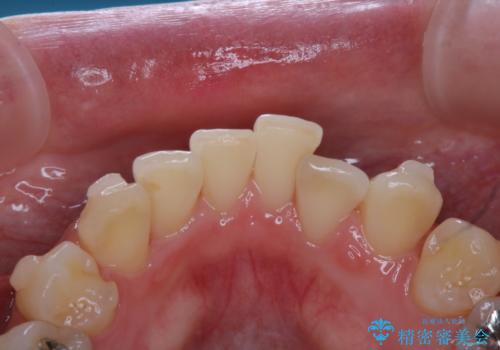

- インビザラインで矯正治療中にクリーニングを希望されました。PMTC60分コースで、クリーニングと歯ブラシ指導を行いました。

磨けているようでも、染出しをして目に見えるプラーク(歯垢)を確認することで、より正しいブラッシング方法を身につけることができます。インビザライン中は、歯にアタッチメントをつけるため、歯の表面がデコボコしてプラークが付きやすい状態になります。毎日のケアでしっかりと汚れを落として虫歯や歯周病・口臭のリスクを減らしていくことが大切です。定期的にメンテナンスを行い、ケアがどれくらい出来ているか確認したり歯科医院で専門的な機械や器具によるPMTCを行うことをおススメします。